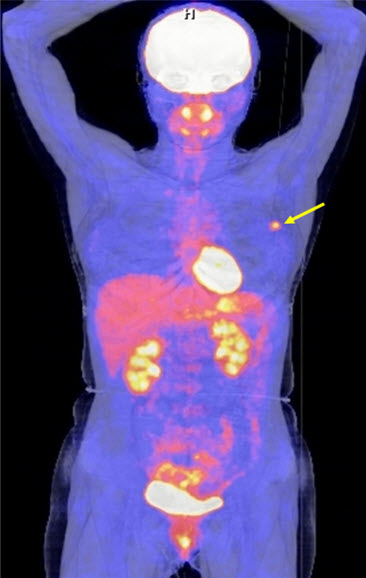

Hình 4 (a, b) cho thấy giá trị của PET/CT trong đánh giá giai đoạn của ung thư vú. Bệnh nhân Nguyễn Th. T. Tr., nữ, 63 tuổi, chẩn đoán là ung thư vú. Kết quả PET/CT toàn thân cho thấy nhiều tổn thương di căn hạch cổ, hạch trung thất, di căn 2 phổi, gan, xương tăng hấp thu FDG.

Hình 4a. Hình PET toàn thân thấy nhiều tổn thương hạch cổ, hạch trung thất (mũi tên vàng), phổi (mũi tên đỏ), gan (mũi tên tím) và xương (mũi tên xanh) tăng hấp thu FDG.

Hình 4b. Hình PET/CT ở mặt phẳng cắt ngang thấy tổn thương di căn phổi (mũi tên đỏ) và di căn gan (mũi tên da cam).